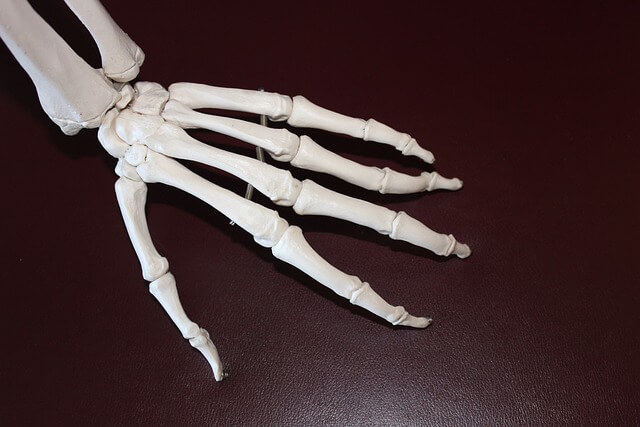

3. 과다 복용 시 부작용

대부분의 사람들에게 안전하게 사용되지만, 일부 사용자에게는 부작용이 발생할 수 있습니다. 일반적인 부작용으로는 다음과 같습니다.

- 소화 불량 : 일부 사용자는 콘드로이친을 섭취한 후 소화 불량이나 복통을 경험할 수 있습니다.

- 알레르기 반응 : 드물게 콘드로이친에 알레르기 반응을 보이는 경우가 있으며, 이 경우 즉시 사용을 중단하고 의사와 상담해야 합니다.

- 혈액 응고 문제 : 콘드로이친은 혈액 응고에 영향을 줄 수 있으므로, 항응고제를 복용 중인 사람은 주의가 필요합니다.